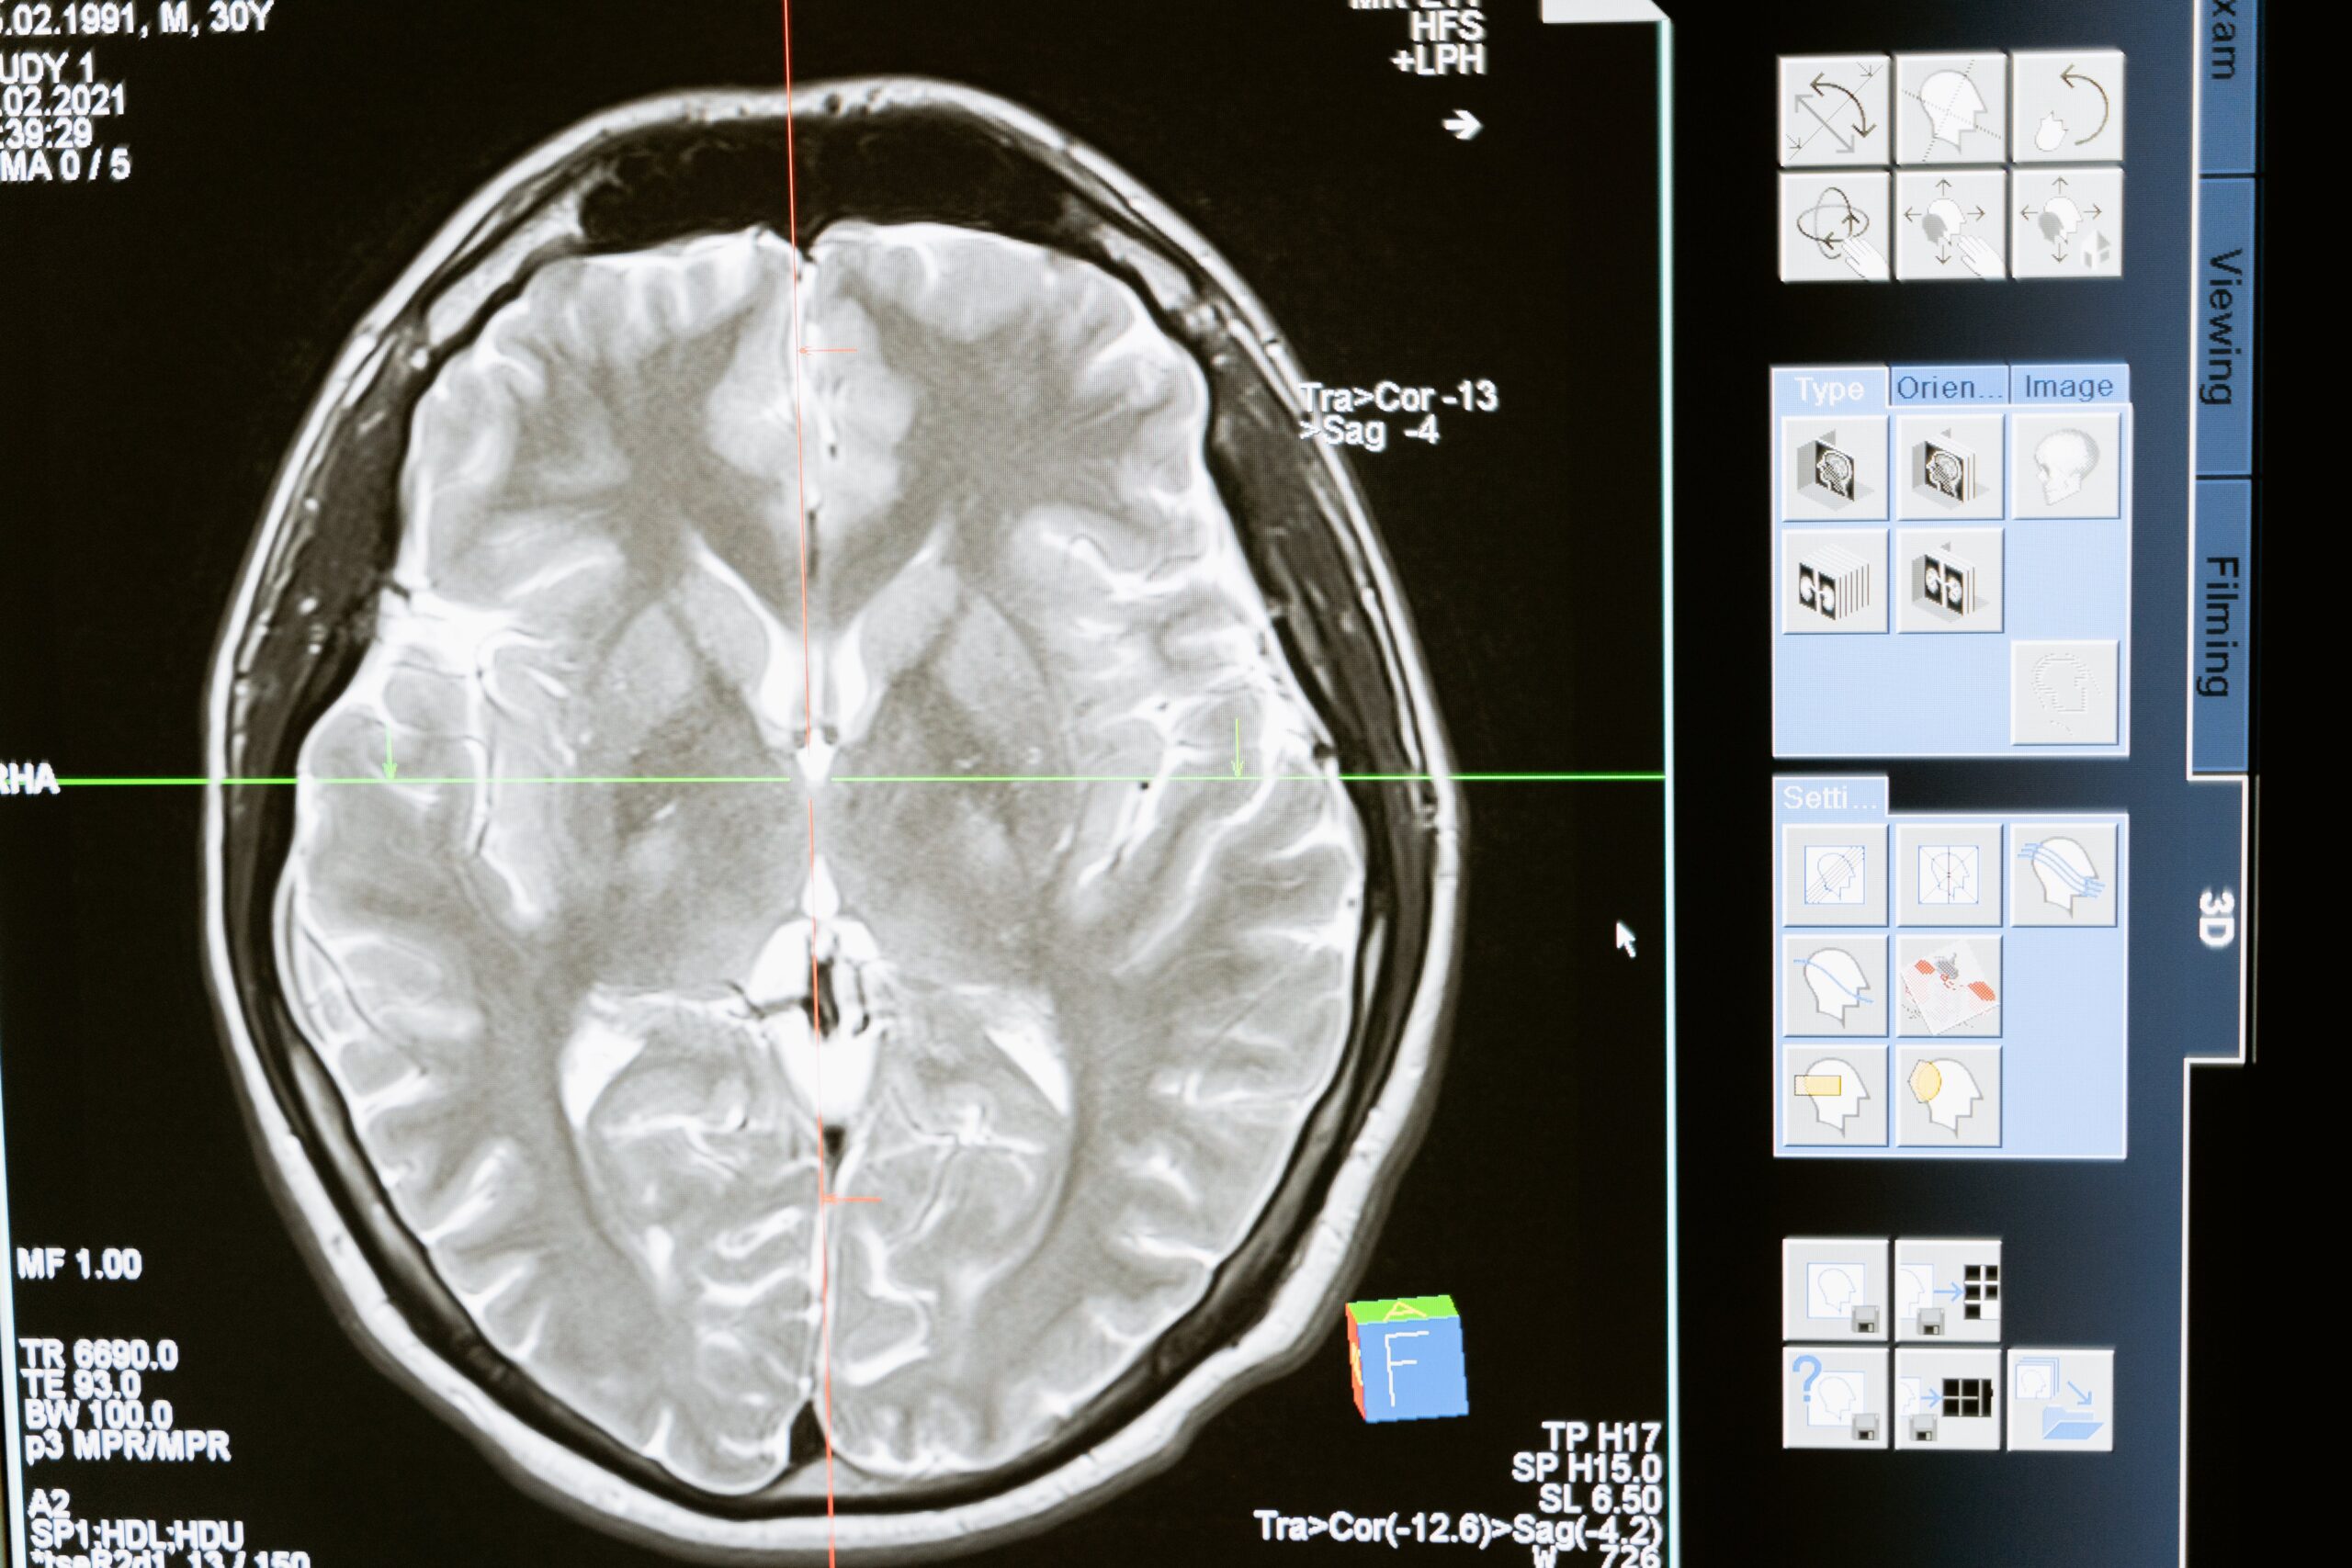

During a stroke, blood flow to part of the brain is interrupted, causing brain cells to die. This can be due to a blocked artery (ischemic stroke) or leaking/burst blood vessel (hemorrhagic stroke). Once brain cells die, the abilities controlled by that area of the brain are impacted. This could include speech, movement, memory, and more depending on the stroke’s severity and location.